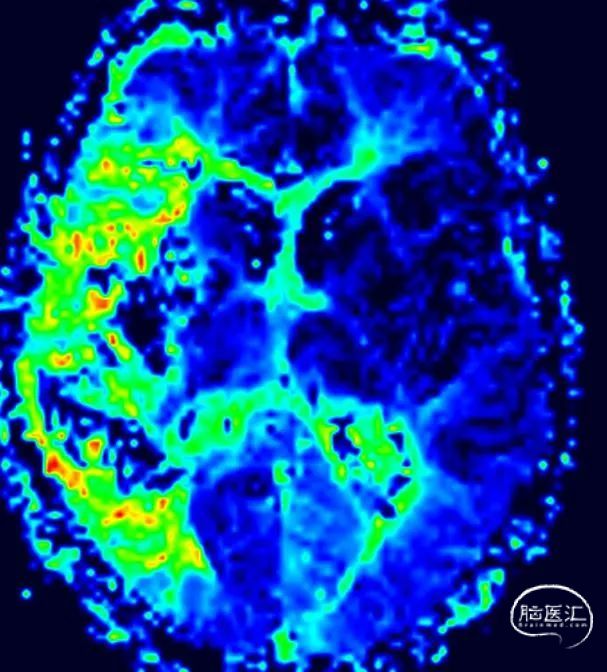

MR灌注

CBF